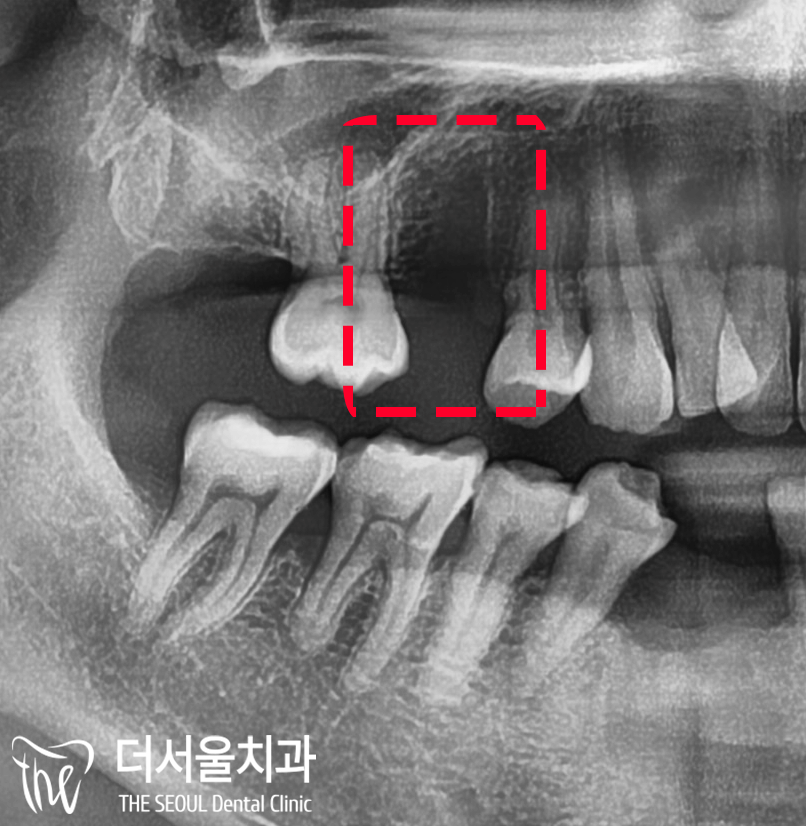

엑스레이로 체크했을 때도

식립하려는 위치에 잘 심어졌네요.

뼈이식 또한 결과가 좋구요. ^^